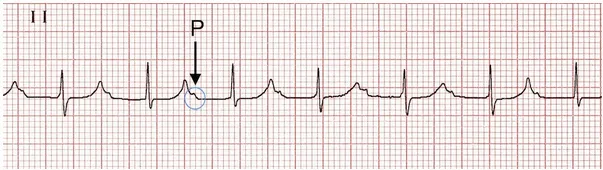

Block nhĩ thất độ 2 là tình trạng gián đoạn dẫn truyền điện tim từ tâm nhĩ xuống tâm thất, có thể gây biến chứng nguy hiểm. Bài viết trình bày về cơ chế điện học của tim, phân loại, nguyên nhân,...

Block nhĩ thất độ 2 là tình trạng gián đoạn dẫn truyền điện tim từ tâm nhĩ xuống tâm thất, có thể gây biến chứng nguy hiểm. Bài viết trình bày về cơ chế điện học của tim, phân loại, nguyên nhân,...